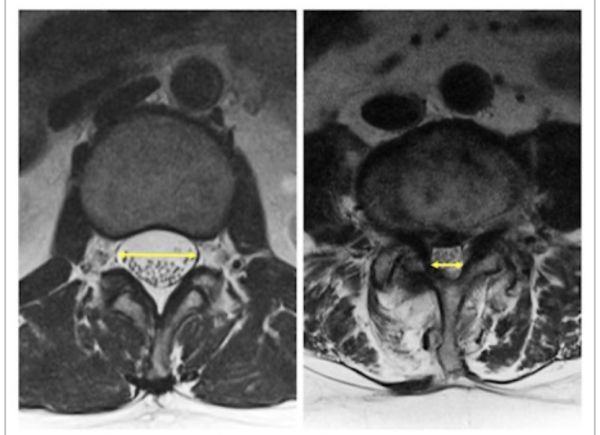

Muayene bulguları içerisinde üzerinde durmamız gereken en önemli unsur radyolojik muayenelerdir. Burada, direkt röntgenler ile beraberinde manyetik rezonans ve bununla beraber gerektiğinde Myelo-MR çekilerek darlıkların nerede ve ne miktarda olduğu tespit edilir.